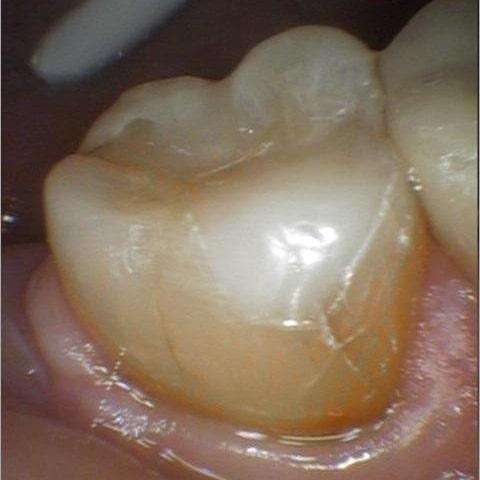

This patient suffered from a combination of acid erosion and grinding, which led to accelerated wear on her lower right molar. The enamel had been lost on the chewing surface and the underlying tooth structure was exposed. A conservative tooth-colored composite filling was placed to restore function and protect the tooth.

After